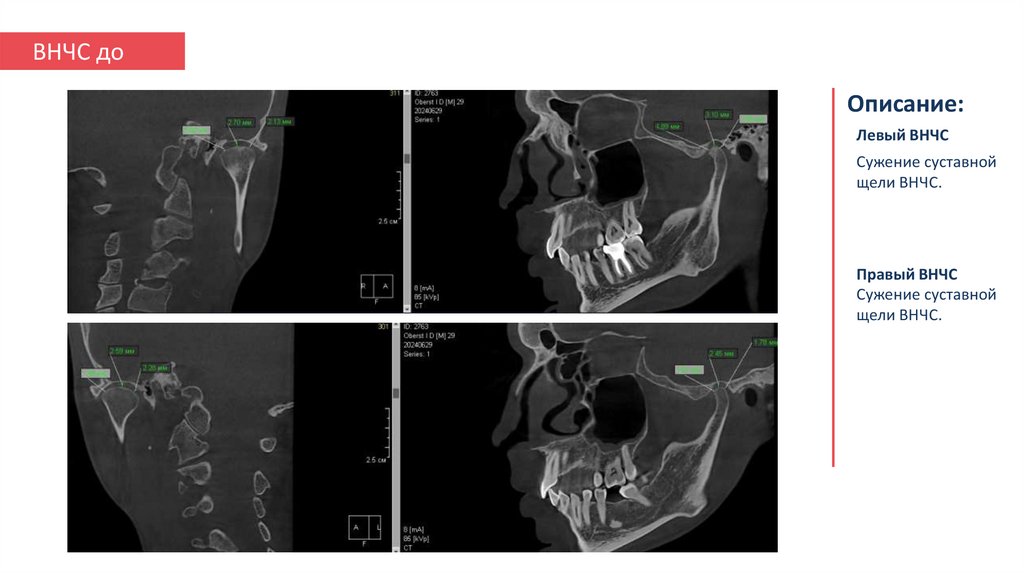

14. ВНЧС до

Описание:

Левый ВНЧС

Сужение суставной

щели ВНЧС.

Правый ВНЧС